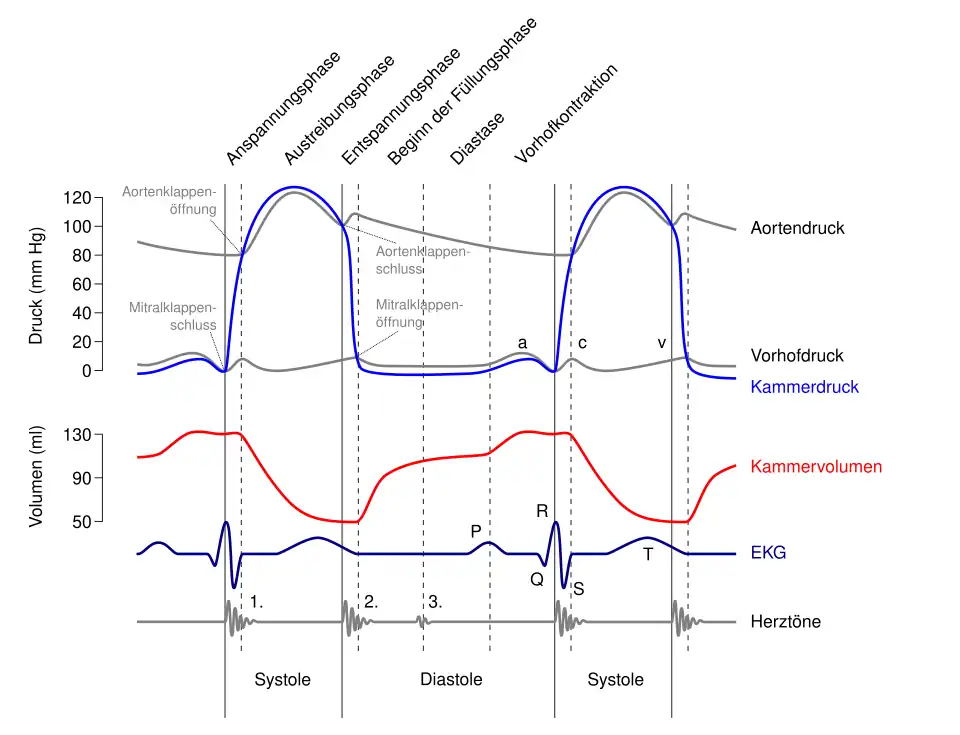

Mechanik der Herzaktion

Das menschliche Herz pumpt in Ruhe etwa das gesamte Blutvolumen des Körpers einmal pro Minute durch den Kreislauf, das sind bei Erwachsenen etwa fünf Liter pro Minute. Bei körperlicher Belastung kann die Pumpleistung etwa auf das Fünffache gesteigert werden, wobei sich der Sauerstoffbedarf entsprechend erhöht. Diese Steigerung wird durch eine Verdoppelung des Schlagvolumens und eine Steigerung der Herzfrequenz um den Faktor 2,5 erreicht.

Bei jeder Pumpaktion fördert jede Kammer und jeder Vorhof etwas mehr als die Hälfte des maximalen Füllungsvolumens, also etwa 50–100 ml Blut. Das ist die Ejektionsfraktion, also der prozentuale Anteil am enddiastolischen Füllungsvolumen, welcher aus der Herzhöhle herausgeworfen wird. Die Herzfrequenz (Schläge/Minute) beträgt in Ruhe 50–80/min (bei Neugeborenen über 120–160) und kann unter Belastung auf über 200/min ansteigen. Liegt ein zu langsamer Herzschlag vor (unter 60/min im Ruhezustand), wird von einer Bradykardie gesprochen. Schlägt das Herz zu schnell (bei Erwachsenen über 100/min im Ruhezustand), spricht man von einer Tachykardie.

Während eines Herzzyklus füllen sich zunächst die Vorhöfe, während gleichzeitig die Kammern das Blut in die Arterien auswerfen. Wenn sich die Kammermuskulatur entspannt, öffnen sich die Segelklappen und das Blut fließt, gesaugt durch den Druckabfall in den Kammern, aus den Vorhöfen in die Kammern. Unterstützt wird dies durch ein Zusammenziehen der Vorhöfe (Vorhofsystole). Es folgt die Kammersystole. Hierbei zieht sich die Kammermuskulatur zusammen, der Druck steigt an, die Segelklappen schließen sich und das Blut kann nur durch die nun geöffneten Taschenklappen in die Arterien ausströmen. Ein Rückfluss des Blutes aus den Arterien während der Entspannungsphase (Diastole) wird durch den Schluss der Taschenklappen verhindert. Die Strömungsrichtung wird also allein durch die Klappen bestimmt.

Das Herzskelett ist ausschlaggebend für die Mechanik der Herzaktion: Aufgrund des Rückstoßes bei der Blutaustreibung ist die Herzspitze im Laufe des gesamten Herzzyklus relativ fixiert und bewegt sich kaum. Somit wird folglich bei einer Kontraktion der Kammermuskulatur (Systole) die Ventilebene nach unten in Richtung der Herzspitze gezogen. In der Erschlaffungsphase der Kammermuskulatur (Diastole) bewegt sich die Ventilebene wieder in Richtung Herzbasis.

Bei der Senkung der Ventilebene wird somit zum einen das Blut aus der Kammer in den Kreislauf ausgeworfen und zum anderen vergrößert sich auch der zugehörige Vorhof. Es kommt zu einem Unterdruck, wodurch Blut aus den großen Venen in die Vorhöfe strömt. Bei der Erschlaffung der Kammermuskulatur hebt sich nun die Ventilebene, wodurch die Kammern passiv über die Blutsäulen der Vorhöfe ausgedehnt werden und sich dadurch zu etwa 70–80 % füllen. Die anschließende Kontraktion der Vorhöfe pumpt nun das restliche Blut in die Kammern und leitet somit einen neuen Herzzyklus ein. Die Vorhofkontraktion ist daher nicht zwingend für das Funktionieren des Herzens nötig, was sich auch daran zeigt, dass (im Gegensatz zum Kammerflimmern) Patienten mit Vorhofflimmern durchaus lebensfähig sind.